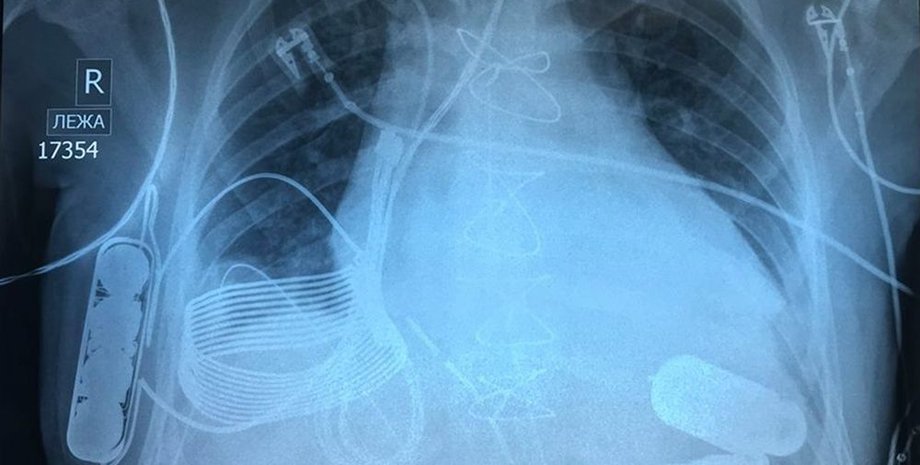

Новое устройство не нуждается в проводе питания благодаря системе зарядки, созданной израильской технологической компанией Leviticus Cardio. Система состоит из индуктивной катушки приемника, аккумулятора внутреннего контроллера — все они имплантированы в грудь пациента. От одного заряда устройство может проработать около восьми часов.